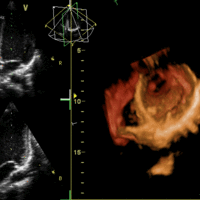

The atrioventricular valves separate the atria from the ventricles and prevent backflow from the ventricles into the atria during systole.

The semilunar valves allow blood to be pumped into the major arteries, but prevent backflow of blood from the arteries into the ventricles.